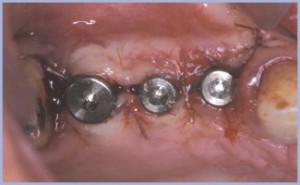

Al terzo quadrante si inseriscono due fixture in posizione -6 e -7 in due fasi chirurgiche (figg. 28-29).

Si eseguono protesi su pilastro naturale e su impianti, non collegate (figg. 30-32).